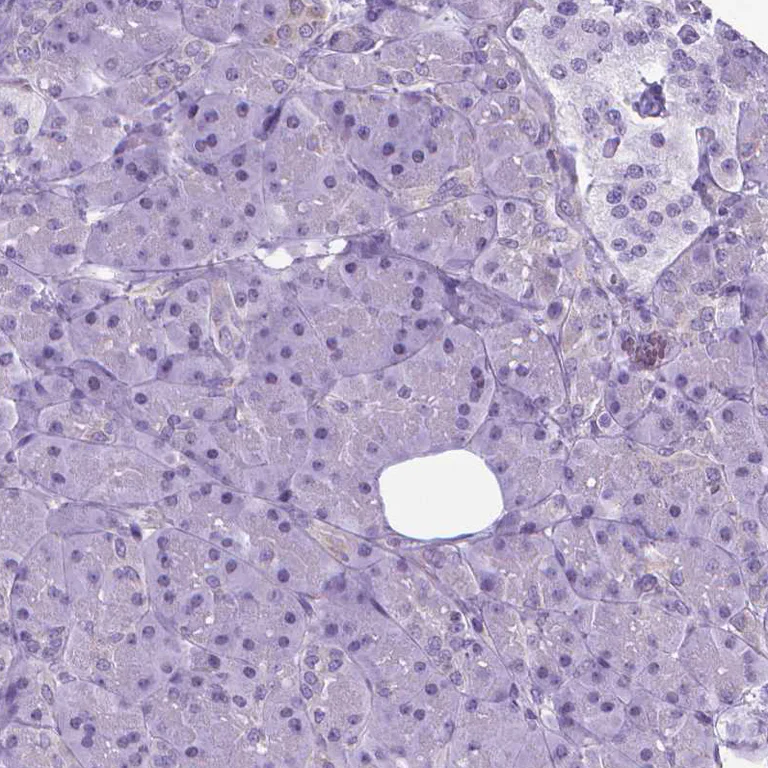

Paraffin-embedded human pancreas tissue stained for POU3F3/Brain1 using ab247159 at 1/200 dilution in immunohistochemical analysis. No positivity in exocrine glandular cells as expected.